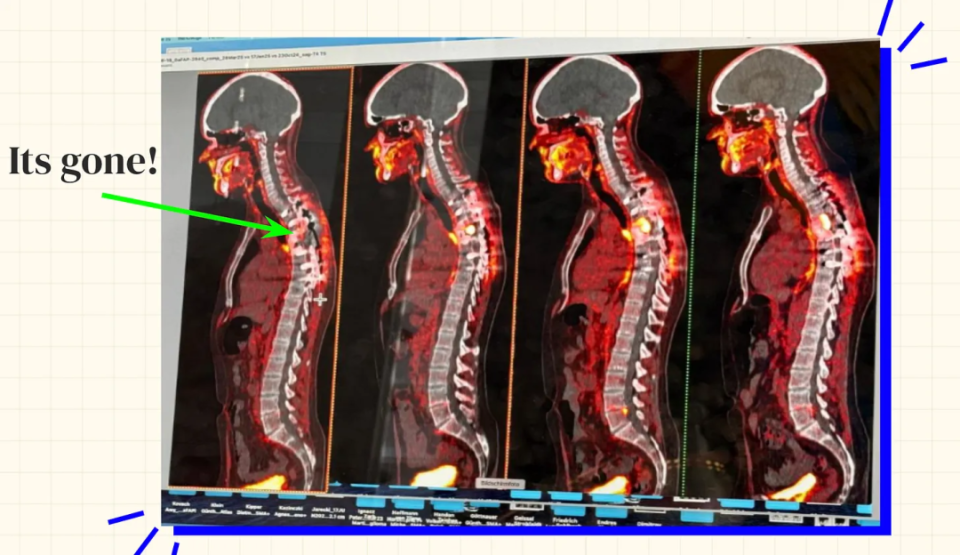

图 | 西德肿瘤的影像(来源:西德)

图 | 西德手术前后的癌症照片,从右至左展示了癌细胞的进展情况(来源:西德)